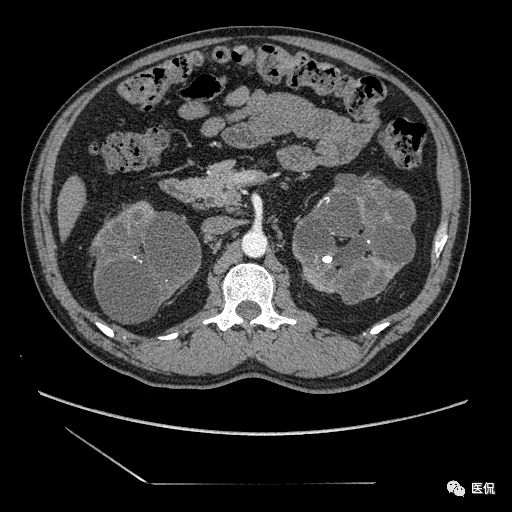

双肾实质可见多发囊性密度灶,其内密度不均匀,并可见钙化灶,增强扫描未见明显强化灶。肾周脂肪间隙清晰,与邻近组织分界清楚。

多囊肾的 CT 表现主要表现为双肾增大,轮廓光滑或有分叶,肾实质内多个大小不等的囊肿呈蜂窝状,多呈水样低密度,增强扫描囊肿本身无强化,而囊肿间正常肾组织增强,对比明显。当囊肿张力过高,使囊壁上毛细血管牵拉破裂出血时,表现为囊肿内稍高密度影,随访CT 值减低。囊壁钙化,表现为点线状高密度影像,随访CT值无变化。有文献报道约 30%病例可并发多囊肝或多囊胰。